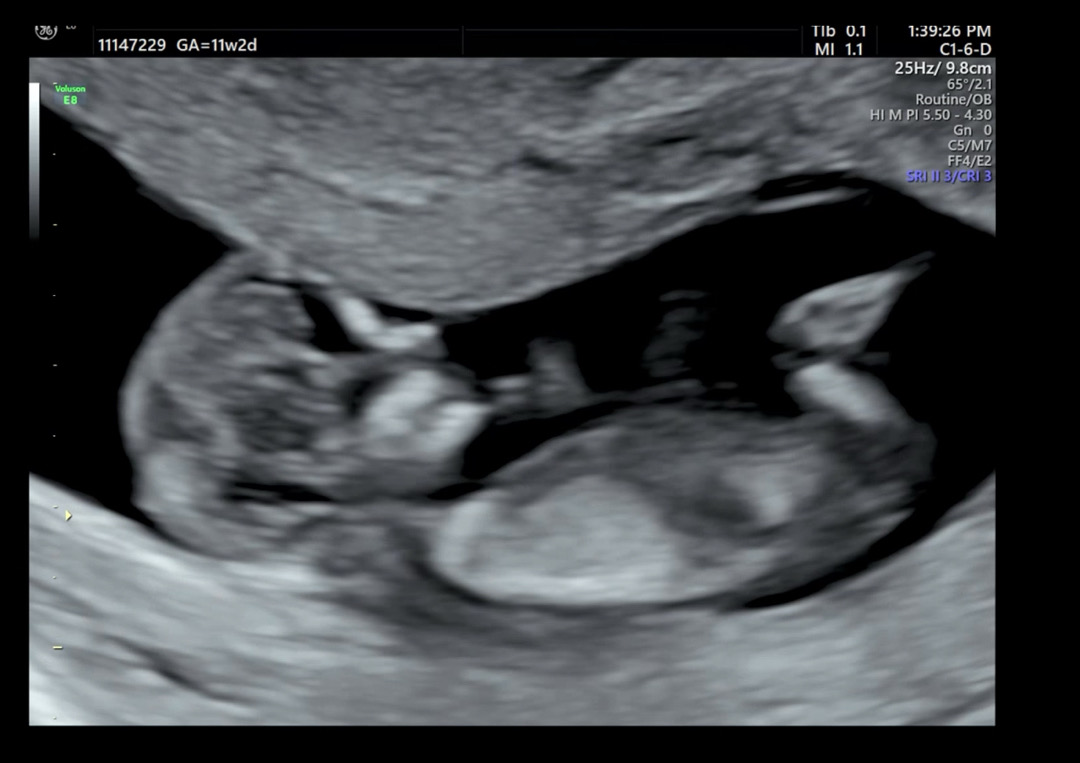

저희 나나 각도법 봐주실 분 부탁드려요😍

12주차 됐는데 궁굼해요! 베동님들 부탁드려요🙏😊

아들같아용

요사진은 아들같아용

안보이는 캡쳐같아요ㅜㅠ 가랑이 중간이 나와야되는데 다리가보여서요

추가사진 더 올려봤는데 요걸로도 안될까용🥲